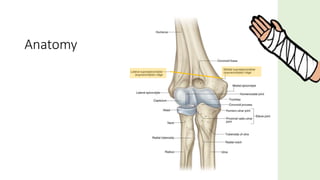

Anatomy